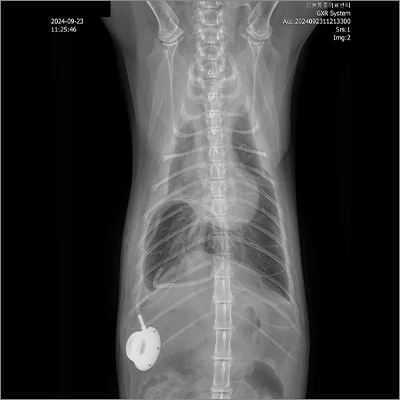

📍 흉관장착

흉관장착 전

흉관장착 후

C-arm 투시 영상장비를 이용해 심장 내부에 기생하는 사상충을 정밀하게 제거합니다